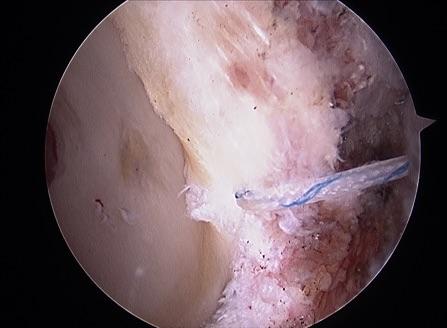

镜下可见盂唇损伤

图片尺寸2667x2000